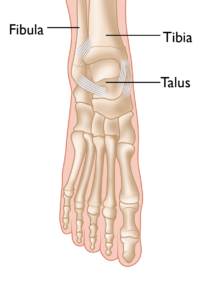

Anatomy of the Ankle Joint

The ankle joint is the point where the tibia (shinbone), fibula (outer ankle bone), and talus (a small bone in the foot) come together. These bones are held in place by ligaments, which function like sturdy ropes, providing stability to the joint by connecting bones and preventing excessive movement. The ankle contains several important ligaments that work together to maintain joint stability and facilitate smooth movement.

The normal skeletal anatomy of the foot and ankle.